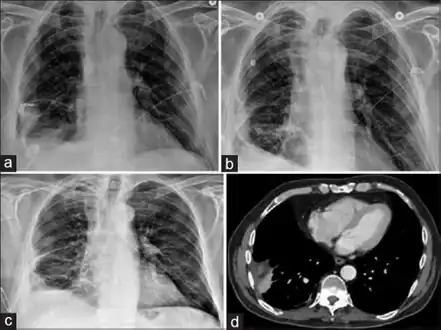

| Progression of empyema | |

Lungs

Empyema with abscess